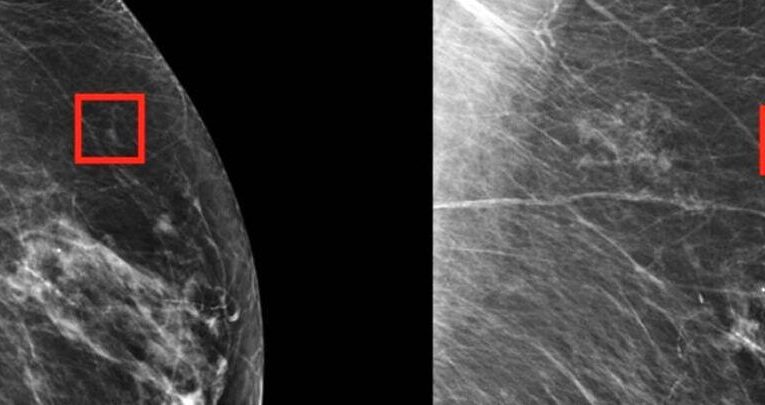

به گزارش آینده مطالعات تازه نشان داده اند که تصویربرداری از سینه به پشتیبانی هوش مصنوعی (AI) پتانسیل افت تعداد قابل توجهی از آن دسته سرطان‌ های سینه ای را دارد که … Read More

هوش مصنوعی می‌تواند مبتلایان به سرطان پستان را از درمان‌های غیرضروری در امان نگه دارد

این مطالعه مشخص می کند که برسی هوش مصنوعی از بافت‌های سرطانی در پیش‌بینی سیر آینده بیماری بهتر از برسی انجام شده توسط پزشکان خبره بوده است.  هوش مصنوعی توانایی … Read More